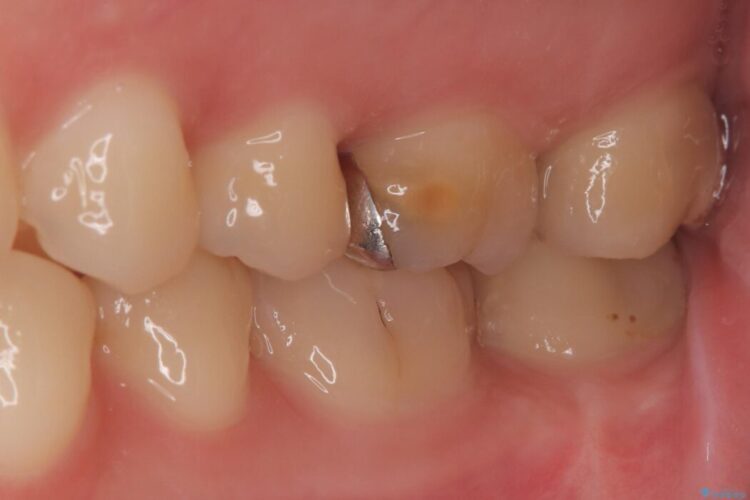

「冷たいものが強くしみる」とご相談にいらした患者様です。

精密検査の結果、非常に深い虫歯があり、通常であれば抜髄が必要な状態でした。

しかし、神経を抜くと歯の寿命が縮まってしまうため、今回は神経の一部を温存する部分的断髄法(VPT)を提案しました。